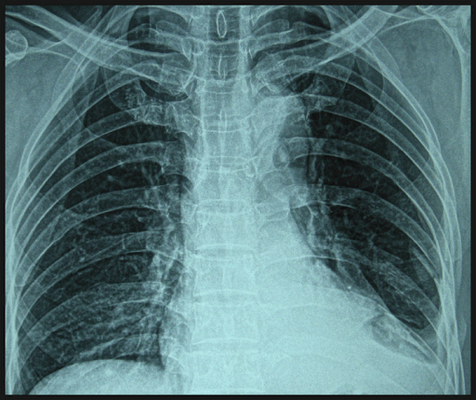

Любая травма грудной клетки опасна для жизни и здоровья, поэтому все пострадавшие даже при удовлетворительном состоянии требуют детального обследования. Диагноз уточняют с помощью рентгенографии грудной клетки. В зависимости от вида травмы назначают консервативное или хирургическое лечение.

Диагностируют ушиб грудной клетки на основании внешних признаков, субъективных ощущений пациента. Чтобы исключить травмирование внутренних органов обязательна рентгенография грудной клетки. Исследование позволяет оценить состояние костных структур, установить расположение переломов, выявить уровень жидкости и газа в плевральной полости и легочной ткани.